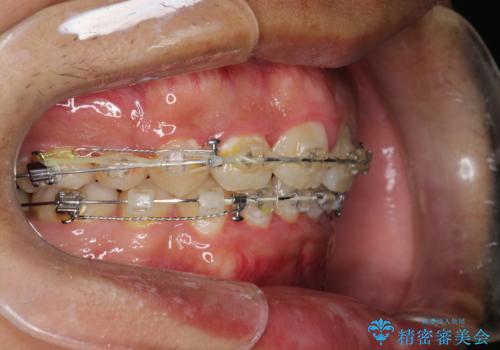

ワイヤー矯正終了時に装置除去と合わせてPMTC

- ワイヤー矯正の終了時にしばらく行っていないためクリーニングも希望されました。装置の除去j時にPMTC60分コースを行いました。

装置を除去すると、エナメル質にダメージがかかることなどがあります。除去の際、一緒にクリーニングを行うことで、エナメル質をなめらかにしたり、歯ぐきの引き締まりが見られます。また、歯ブラシだけでは取り除けない汚れも取り除きますので、歯の表面がツルツルになります。矯正治療中・終了時には合わせてPMTCを行うことがおすすめです。